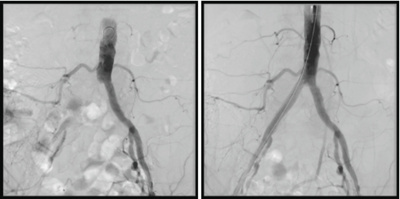

Beckenarterie

zentrum-fuer-mikrotherapie-beckenarterie

Verschluss der rechten Beckenarterie (links), welche durch den Mikrotherapeuten mittels einer Gefässstütze (Stent) erfolgreich geöffnet werden konnte.

© Interventionelle Radiologie - Swiss Intervention